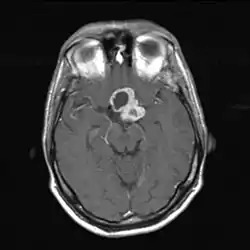

Магнитно-резонансная томография

Магнитно-резонансная томография (МРТ) даёт возможность определить точные размеры краниофарингиом, соотношение их узловой и кистозной частей, размеры и локализацию. Также МРТ даёт представление о состоянии желудочковой системы, наличии или отсутствии гидроцефалии, топографо-анатомическом взаимоотношении опухоли и дна III желудочка[32].

Сигнал от данного новообразования вариабелен[35]. В большинстве случаев кистозный компонент имеет гипоинтенсивный сигнал в режиме Т1 и гиперинтенсивный — в режиме Т2. При наличии высокой концентрации белка, продуктов распада крови, холестерина сигнал от кистозной жидкости может существенно меняться[36]. Это проявляется в повышении интенсивности сигнала. Данная особенность является высокоспецифичной именно для краниофарингиом. В режиме Т2 яркость сигнала может варьировать от гипер- до изоинтенсивного[32].

Солидная часть краниофарингиом в большинстве случаев не отличается по интенсивности сигнала от вещества мозга. При введении контрастных препаратов плотность сигнала усиливается[32].

При эндоселлярных краниофарингиомах размеры турецкого седла увеличены. Распространяясь вверх, новообразование заполняет область хиазмальных цистерн, в той или иной степени поддавливает дно III желудочка. Супраселлярная часть краниофарингиом чаще кистозная. Кисты могут распространяться на основание передней черепной ямки, перивентрикулярно или определяться внутри узловой части опухоли. Краниофарингиома чаще всего хорошо отграничена от прилежащего мозгового вещества[32].

При стебельных краниофарингиомах обнаруживаются характерная асимметрия, значительная величина и распространение по основанию мозга, частичное внедрение в полость боковых желудочков. Локализуясь в полости бокового желудочка, кисты могут тампонировать его[32].